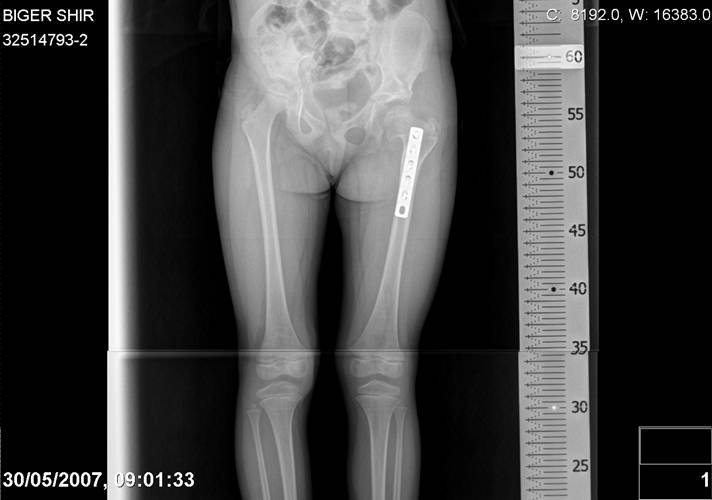

Navernoe Dega

Chto by ne byt goloslovnym posilau vam svoi sluchai gde sdelal vse chto napisal vyshe